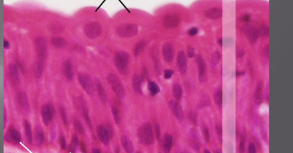

transitional

If filled with urine, stretched so squamous-like

If empty, cells appear columnar

Found in ureter, urethra, bladder